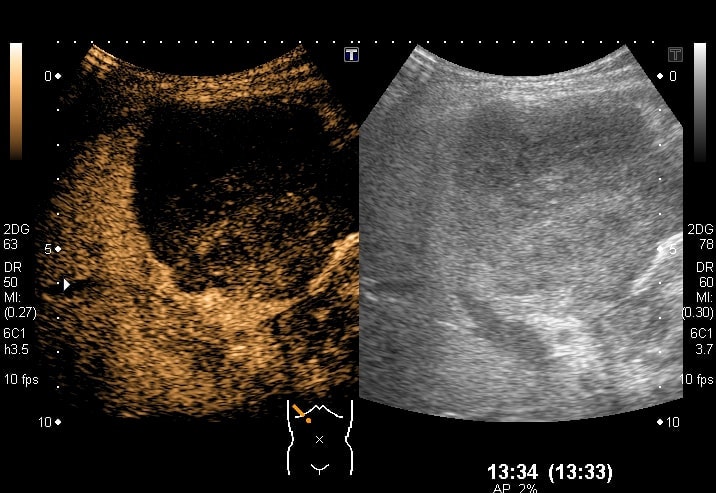

エコー検査(肝臓)